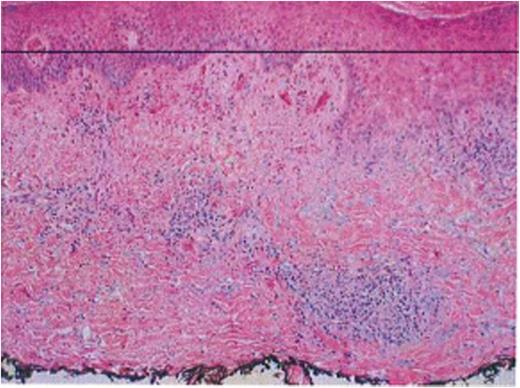

A 69-years-old woman with well controlled CLL presented with pruritic, papular eruptions & ulcerations over extremities and back (Figure 1). She denied asthma or atopy, insect bite, or new medications. Skin biopsy (Figure 2) revealed perivascular & interstitial infiltrate composed of lymphocytes, histiocytes, neutrophils and eosinophils.

Well's syndrome is often described as exaggerated response to insect bite; it may occur without an inciting event, commonly involves extremities, may precede or follow the diagnosis of CLL and has no association with disease course (2). The lesions range from itchy papules, plaques to edematous vesiculo-bullous lesions and panniculitis or ulcerations (3) and can result in disfiguring skin atrophy (4). Pathology reveals eosinophilic or lymphohistiocytic infiltrates (5). Use of glucocorticoids, antihistamines, immunoglobulins, dapsone, ultra violet-B therapy for treatment has been described (2, 5) and may require prolonged treatment (6). Multiple recurrences are often seen in recalcitrant cases (7).